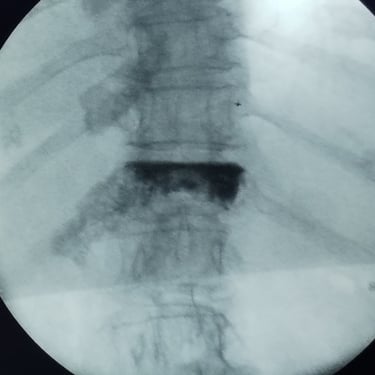

🧠 Vertebroplastia | Tratamiento de Fractura Vertebral por Osteoporosis.

La vertebroplastia alivia el dolor por fracturas vertebrales osteoporóticas mediante la inyección de cemento óseo que estabiliza la vértebra. Es un procedimiento mínimamente invasivo y seguro, que brinda mejoría inmediata del dolor y favorece la recuperación funcional.